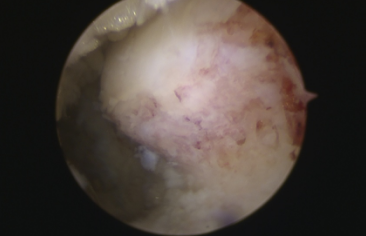

镜下刨削刺激病变的距骨软骨

镜下打入锚钉固定距腓前韧带

术中,探查见关节腔大量增生病变滑膜组织,距骨软骨面多处软骨剥脱变性,明显的外侧副韧带损伤后继发关节炎表现。手术医生在踝关节镜下刨削刺激病变的距骨软骨,打入锚钉固定距腓前韧带,圆满完成手术。